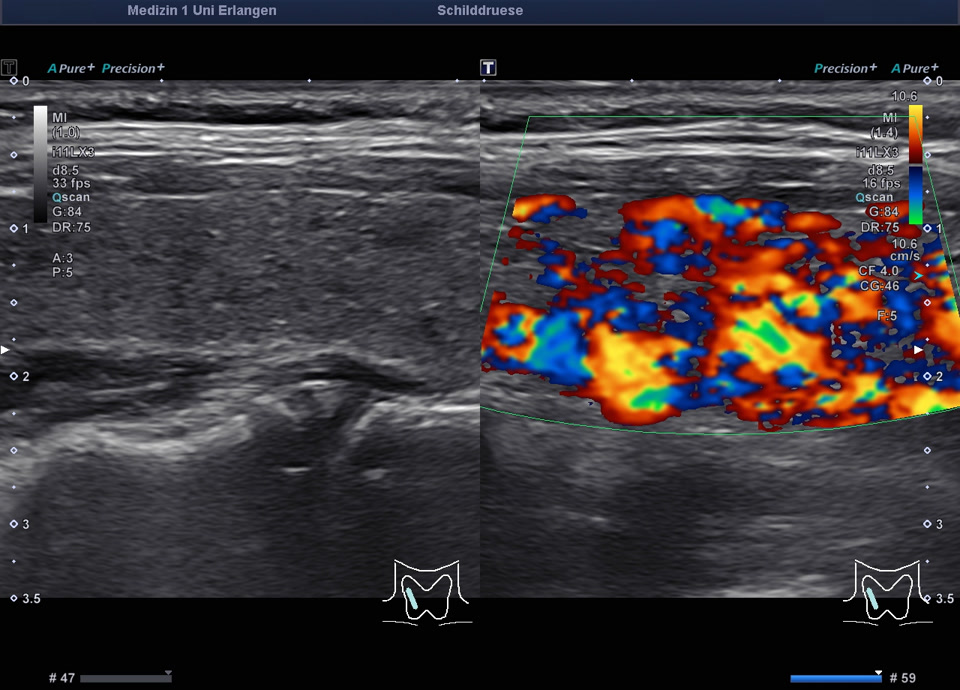

36-jähriger Patient mit Tremor, Tachykardie, Exophthalmus und Gewichtsverlust. Sonographisch stellt sich die Schilddrüse beidseits mit echoarmer inhomogener Parenchymstruktur dar. Gesamtvolumen 20,5 ml. Farbdopplersonographisch hypervaskularisiert. Laborbefunde: basales TSH erniedrigt, T3/fT4 erhöht, TRAK positiv. Befundkonstellation vereinbar mit M. Basedow. Unter Therapie mit Thiamazol und Propranolol beschwerdefrei. Bei Verlaufskontrolle zwei Jahre später sonographisch echoreiches minimal inhomogenes Parenchym bei normalem Volumen (15 ml).